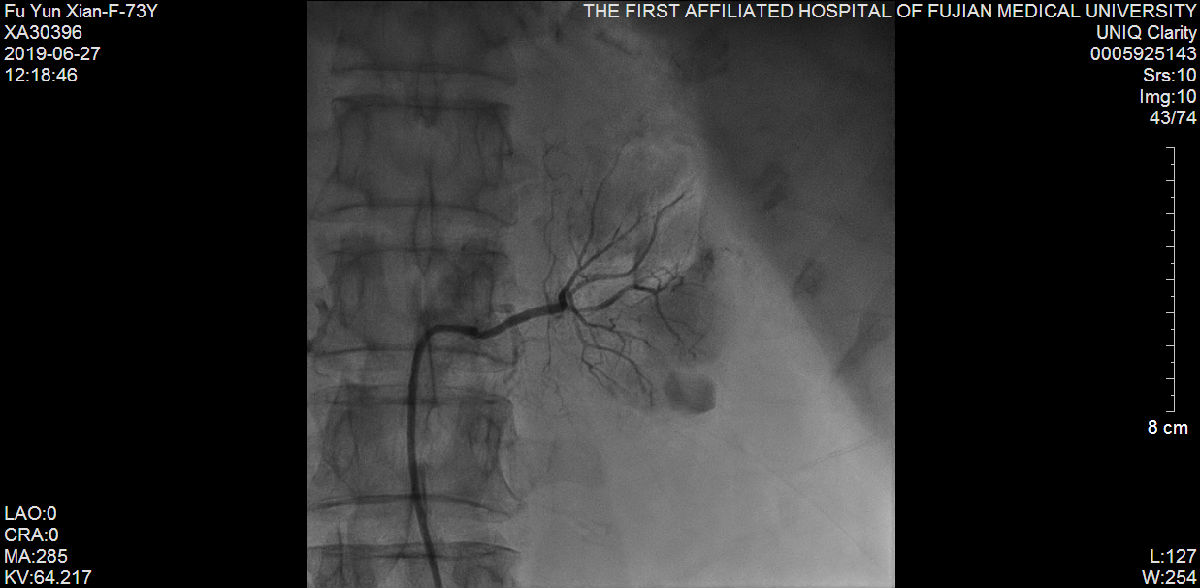

随后,苏津自教授、蔡瀚医师为傅阿姨进行介入手术:肾动脉造影显示双侧肾脏萎缩,右侧肾脏具备进行RDN的条件;而冠状动脉造影显示营养心脏的其中一条主干血管——前降支血管近端99%狭窄伴冠状动脉瘤样扩张。